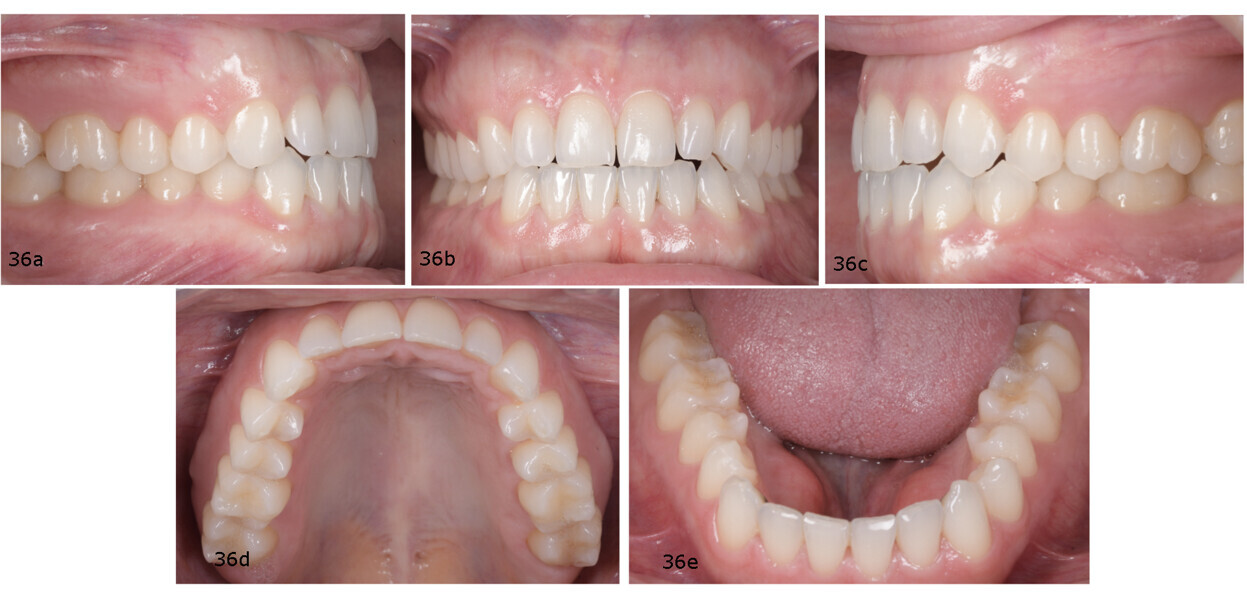

She presented with a symmetrical face, insufficient incisor display at rest and increased gingival display in the posterior segments during smiling. Hypertrophy of the masseter muscles was noted (Fig. 35). Class I molar and canine relationships, well-aligned arches and a favourable arch form were observed. The dental midlines were centred. However, there was a tendency towards anterior open bite, absence of both overjet and overbite, and negative torque of the maxillary incisors. Additionally, the patient exhibited signs of dental wear and mandibular tori—both common findings in patients with bruxism or clenching habits (Fig. 36).

Extra-orally, two aspects are worth highlighting: the significant improvement in the smile, in that the patient no longer showed posterior gingiva, owing to intrusion of the maxillary posterior teeth; and the slimmer facial appearance, thanks to muscle relaxation and reduction in the size of the masseter muscles (Fig. 47). Intra-orally, Class I molar and canine relationships had been achieved, and the anterior open bite had been closed, resulting in proper overjet and overbite. The positive torque applied to the maxillary and mandibular posterior segments had improved the arch form. The maxillary incisors were proclined (U1–PP from 105° pretreatment to 112° post-treatment) and the mandibular incisors retroclined (IMPA from 98° pretreatment to 93° post-treatment; Fig. 48).